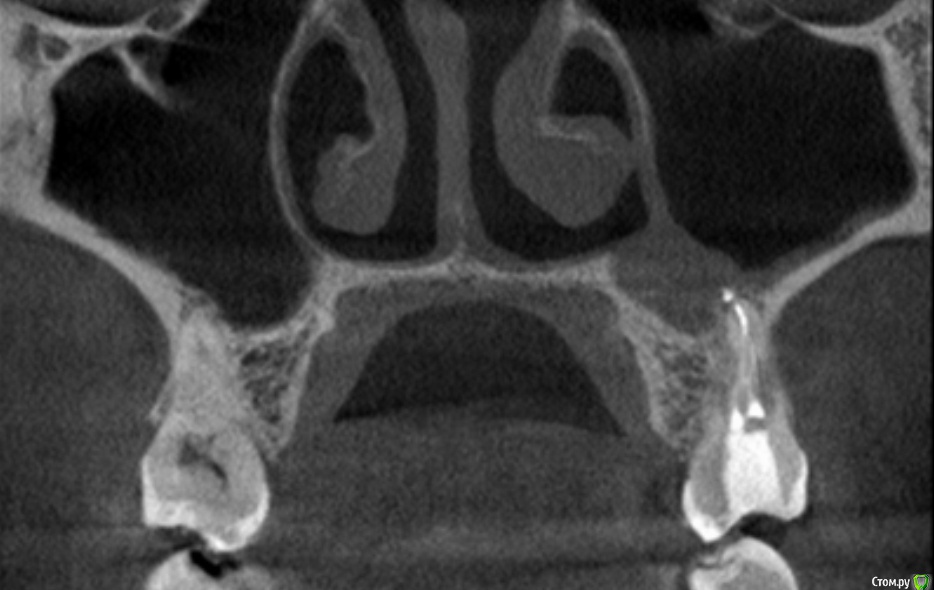

3) Через несколько месяцев после пломбировки к/к боль усилилась, я сделала дентальную КТ, на которой была обнаружена киста гайморовой пазухи и небольшое разряжение у корней зуб (также оказалось, что на по ОПТГ, сделанной перед самой пломбировкой к/к киста была уже в пазухе, но стоматолог не увидел ее на снимке).

киста на КТ

post-50922-0-15482100-1517781260_thumb.jpg